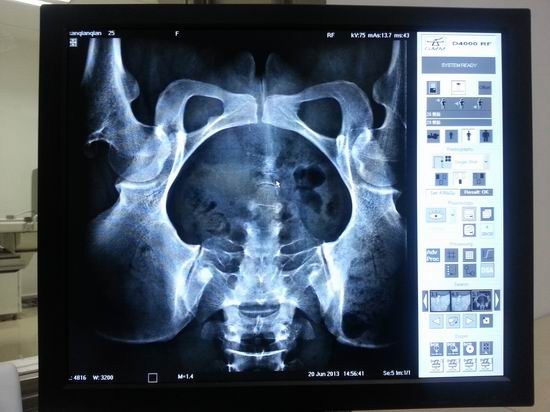

名称:多功能动态平板数字化X线影像系统OPERA FP

主要功能GMM公司的OPERA动态数字平板多功能X线机是一台高度综合完整的设备,装备了专业的图像采集和处理系统,采用碘化铯+非晶硅平板探测器,采集速达到15帧/秒,不但影像效果更加清晰流畅,而且因系统所需X线剂量减少而大大减少病人和医生的放射损伤。其性能全面覆盖放射科所有的临床检查,可进行数字拍片、数字透视、倾斜摄影、数字点片成像(消化和泌尿系统)、数字减影等检查。